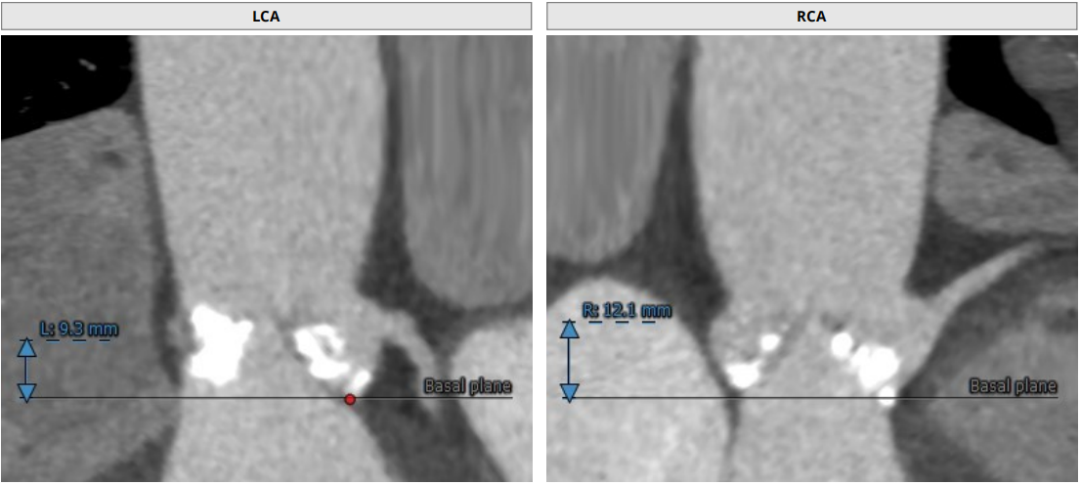

类TYPE2型二叶瓣,极重度钙化,左冠高度稍低,右冠高度可,升主动脉增宽,最宽处约40mm,心脏角度不大,左室大,心尖部局部心肌薄弱作。

1、左冠开口低,冠脉风险偏高

2.冠脉风险:瓣叶较长,右冠高度尚可,左冠9.3mm偏低,但由于钙化分布广且重,瓣叶可能不会被推挤到冠脉开口,术中根据球扩进一步明确。